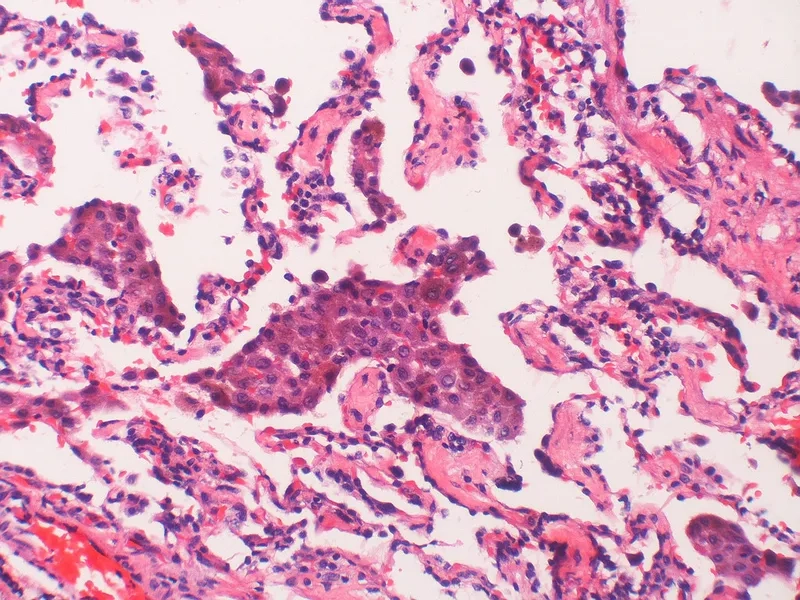

Lymphangioleiomyomatosis (LAM) - A rare lung disease in women

Medical illustration of LAM disease awareness

Image of the disease Lymphangioleiomyomatosis